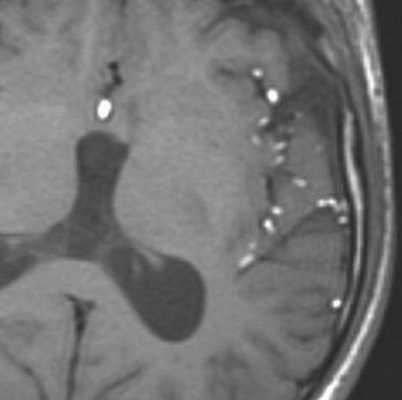

МРТ: киста кармана Ратке. На Т1-взвешенном сагиттальном изображении, полученном до введения контраста, заметно четко очерченное образование в области турецкого седла - с распространением в супраселлярную цистерну. Отмечается гомогенно высокая интенсивность сигнала в образовании по сравнению с паренхимой головного мозга.

Т1-взвешенное сагиттальное изображение, полученное до контрастного усиления: видна хорошо определяемая киста в зоне турецкого седла, изоинтенсивная спинно-мозговой жидкости. Отмечается соответствующая норме высокая интенсивность сигнала задней доли гипофиза сзади.

На Т1-взвешенном корональном изображении она видна рамером чуть менее сантиметра в центральной части турецкого седла. Слегка гиперинтенсивна по сравнению со спинно-мозговой жидкостью.

На этом Т2-взвешенном изображении она изоинтенсивна спинно-мозговой жидкости.

Крупная гиперинтенсивна по сравнению со спинно-мозговой жидкостью на аксиальном протонно-взвешенном изображении. Отмечается расширение турецкого седла с латеральным отклонением чуть заслоненной, но проходимой кавернозной частью внутренней сонной артерии.